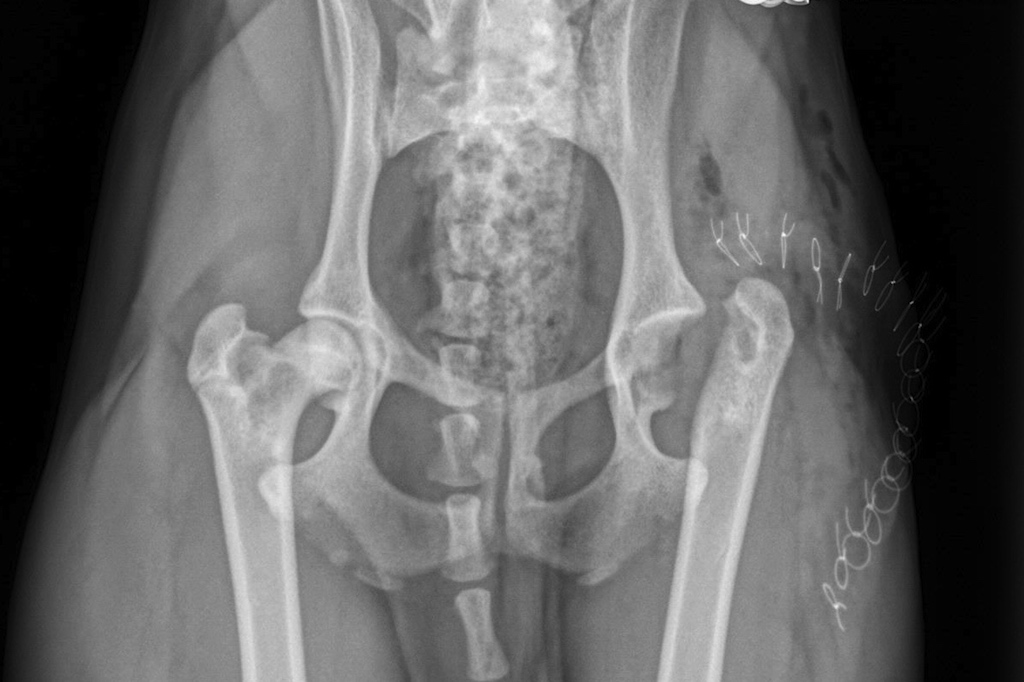

Le vétérinaire commencera par des palpations pour identifier la source de la douleur. Il vérifiera également l’atrophie musculaire, un signe de mauvaise utilisation de la patte. Selon l’examen, des radiographies seront nécessaires pour évaluer les articulations et les os. Les résultats seront connus en 15 à 20 minutes. Les radiographies montrent des signes typiques comme une déformation du col et de la tête fémorale, ainsi que des changements d’opacité et, parfois, une fracture. Le diagnostic repose sur l’examen clinique, les radiographies et l’âge du chien.